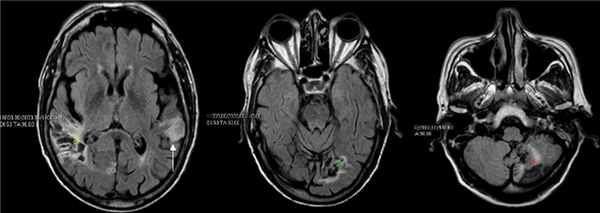

- проведение магнитно-резонансной и компьютерной томографии (детальное изучение мозга, его состояния и возможных отклонений);

В наш век компьютерной и магнитно-резонансной диагностики данные методики могут без труда определить наличие или отсутствие очага нарушения кровообращения, опухоли или черепно-мозговой травмы, локализацию, выраженность процесса, что позволяет эффективнее разработать методы лечения для каждого конкретного больного.

Также, как правило, назначается лучевая диагностика головного мозга, КТ или МРТ.

Визуализация мозга (например, КТ или МРТ с ангиографией или без нее) необходима для определения центральных поражений (например, инфаркта, кровоизлияния, объемного внутричерепного процесса), а также выявления атрофии коры, характерной для дегенеративных заболеваний.